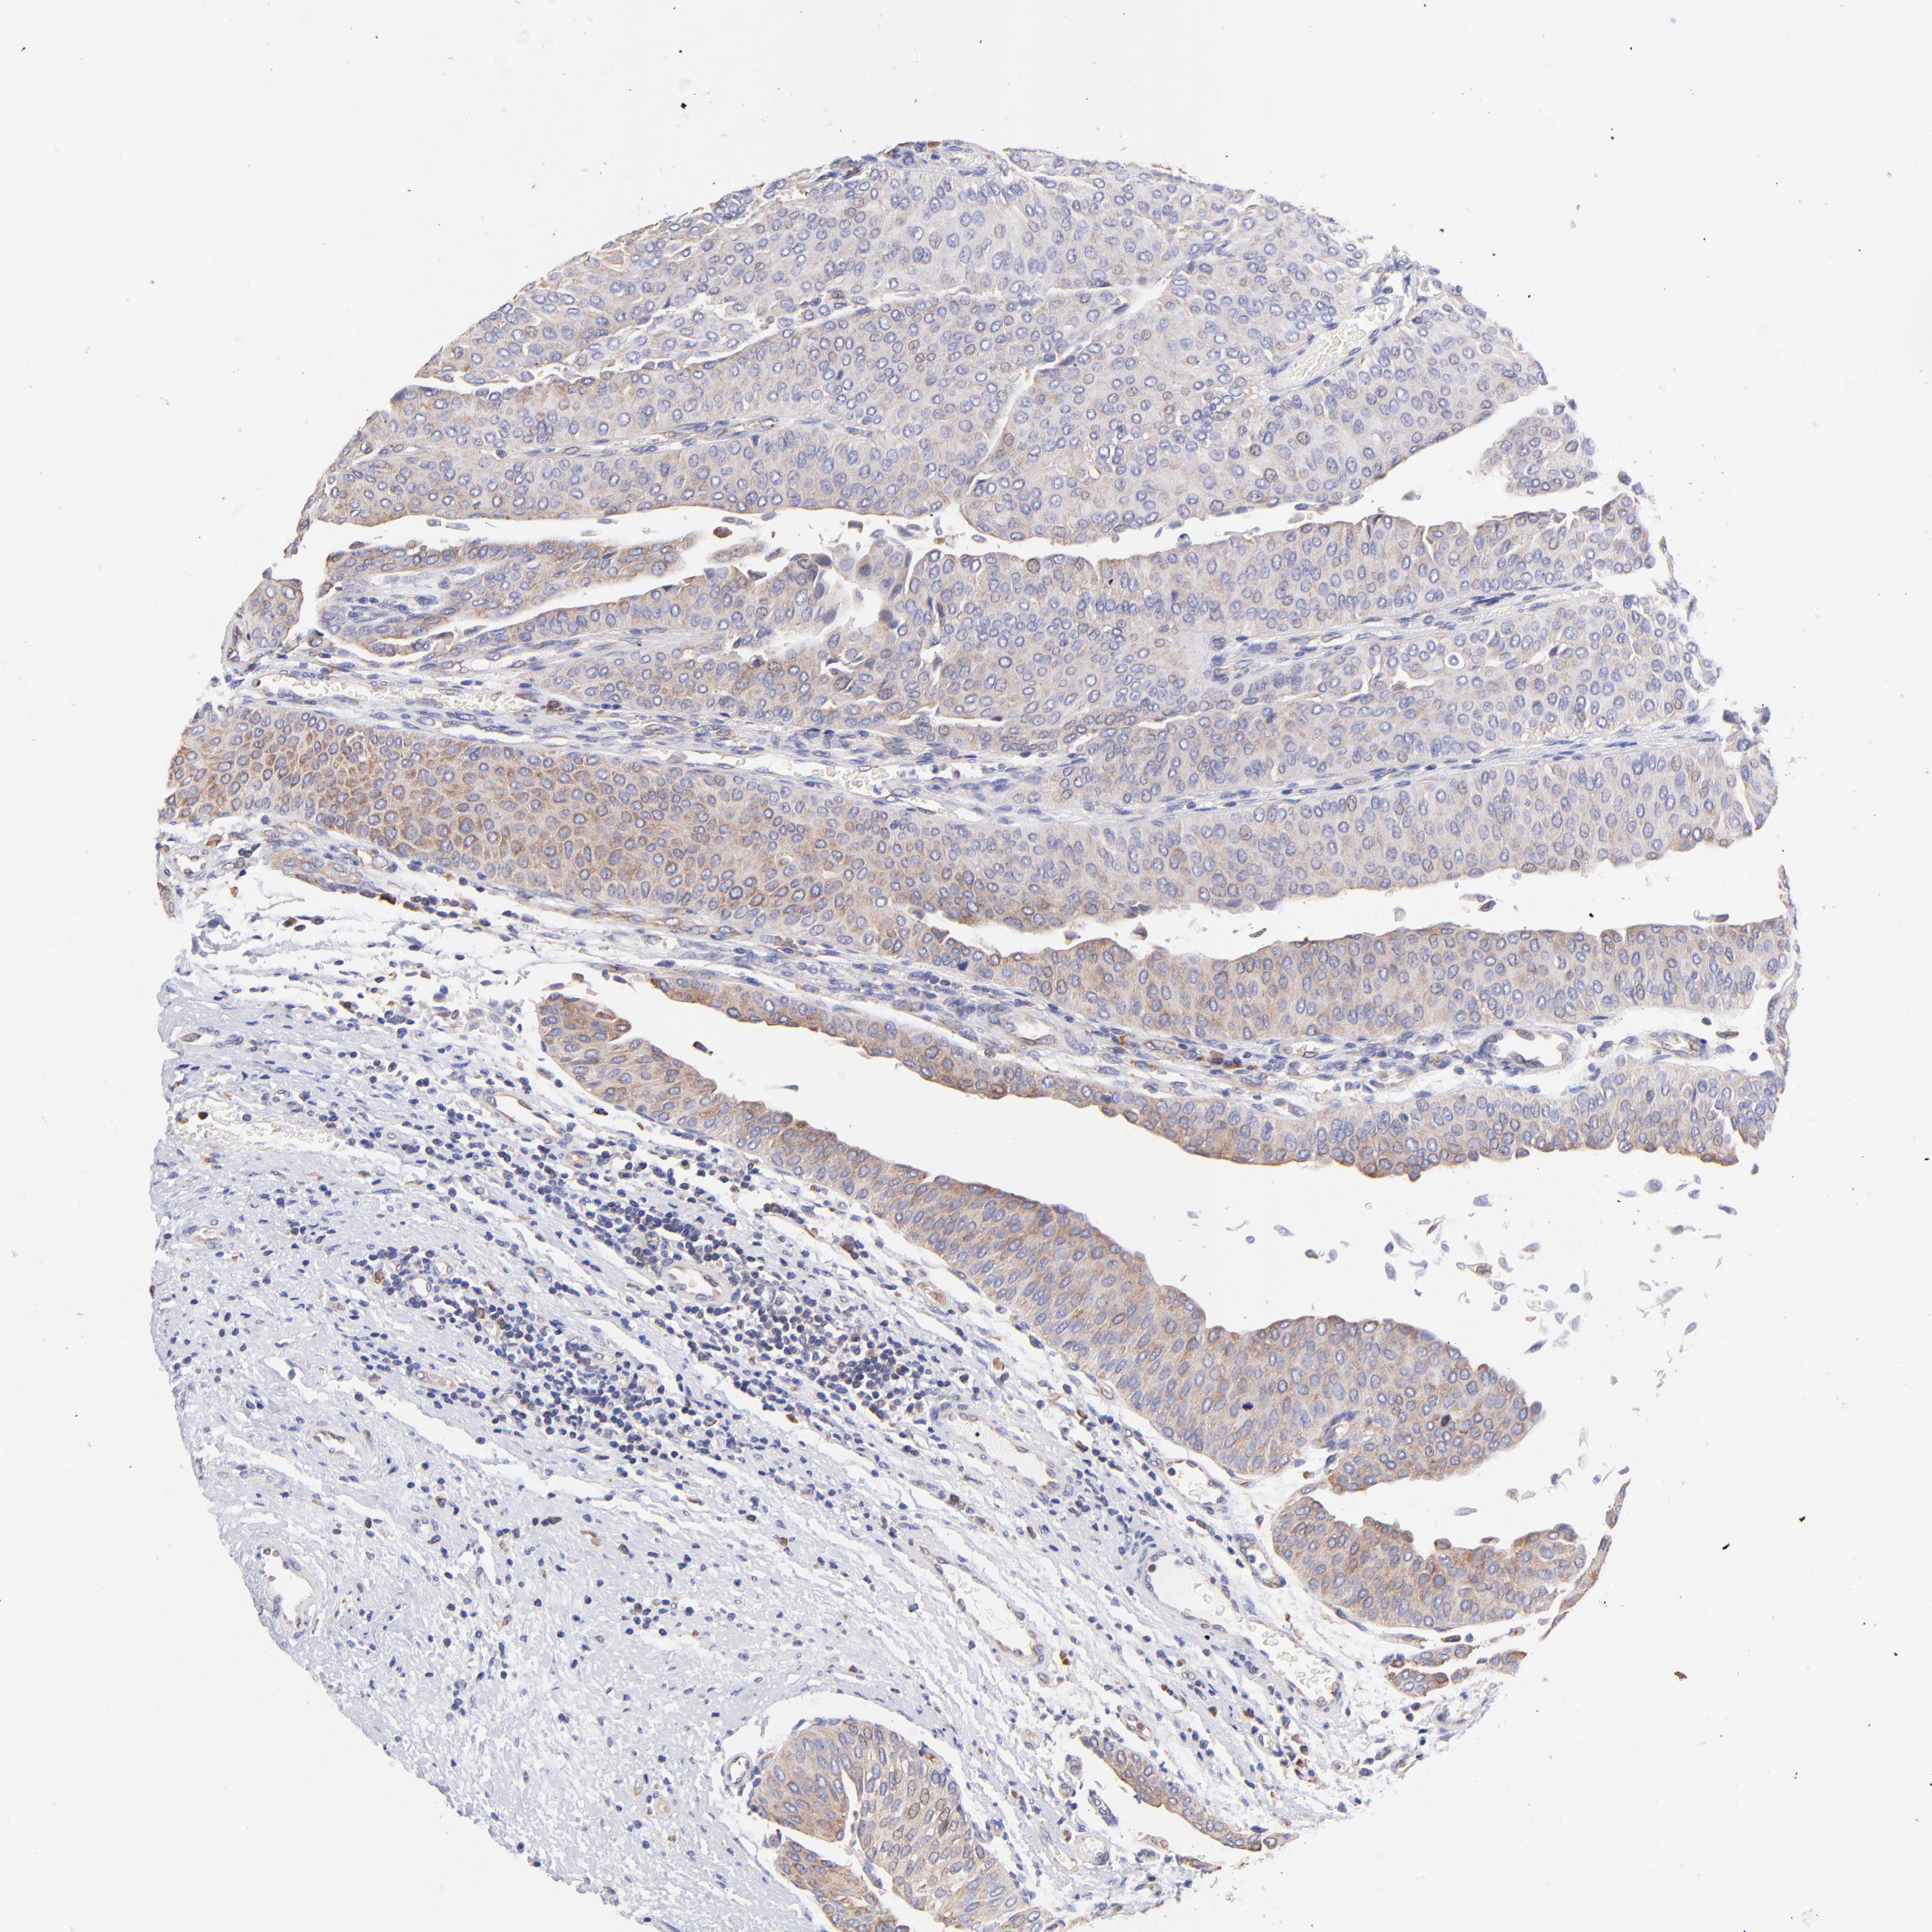

UROTHELIAL CANCER - Protein expressioni

A mouse-over function shows sample information and annotation data. Click on an image to view it in a full screen mode. Samples can be filtered based on level of antibody staining by selecting one or several of the following categories: high, medium, low and not detected. The assay and annotation is described here.

Note that samples used for immunohistochemistry by the Human Protein Atlas do not correspond to samples in the TCGA dataset.

Antibody stainingi

Antibody staining in the annotated cell types in the current human tissue is reported as not detected, low, medium, or high, based on conventional immunohistochemistry profiling in selected tissues. This score is based on the combination of the staining intensity and fraction of stained cells.

Each image is clickable and will lead to virtual microscopy that enables deeper exploration of all samples and also displays staining intensity scores, fraction scores and subcellular localization as well as patient and tissue information for each sample.

Antibody HPA002651

Staining

High

Medium

Low

Not detected

Intensity

Strong

Moderate

Weak

Negative

Quantity

>75%

75%-25%

<25%

None

Location

Nuclear

Cytoplasmic/membranous

Cytoplasmic/membranous,nuclear

Urothelial carcinoma, High grade

Urothelial carcinoma, Low grade